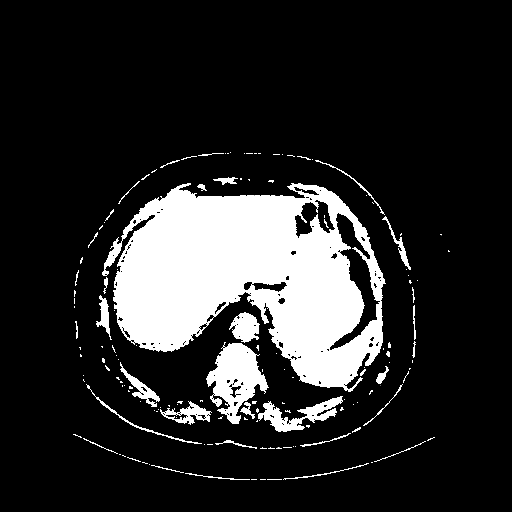

Original NATIVE CT scan (input)

Full window (WL 1023.5, WW 4095 β†’ Low βˆ’1024, High +3071)

Actual HU range: [-1024.0, 3071.0]